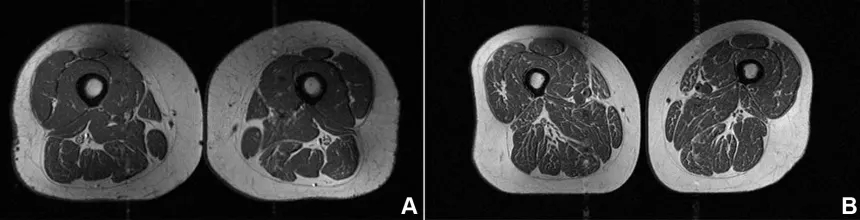

Η γυναίκα με 87,1% υπερεπεξεργασμένα τρόφιμα στη διατροφή της (A στην εικόνα παρακάτω) είχε BMI 32,6 και χαμηλότερη φυσική δραστηριότητα από τη δεύτερη γυναίκα (B στην εικόνα), η οποία είχε BMI 31,8 και 29,5% υπερεπεξεργασμένα τρόφιμα. Παρ’ όλα αυτά, η πρώτη εμφάνιζε πολύ πιο έντονη λιπώδη διήθηση στους μηρούς.

Σύμφωνα με τον επικεφαλής της μελέτης δρ. Thomas Link, καθηγητή στο UCSF Department of Radiology and Biomedical Imaging, η συνολική θερμιδική πρόσληψη δεν φάνηκε να επηρεάζει το αποτέλεσμα.

«Σε όλη τη μελέτη, όσο περισσότερα υπερεπεξεργασμένα τρόφιμα κατανάλωνε κάποιος, τόσο περισσότερη ενδομυϊκή λιπώδης διήθηση είχε, ανεξάρτητα από τις θερμίδες», ανέφερε.